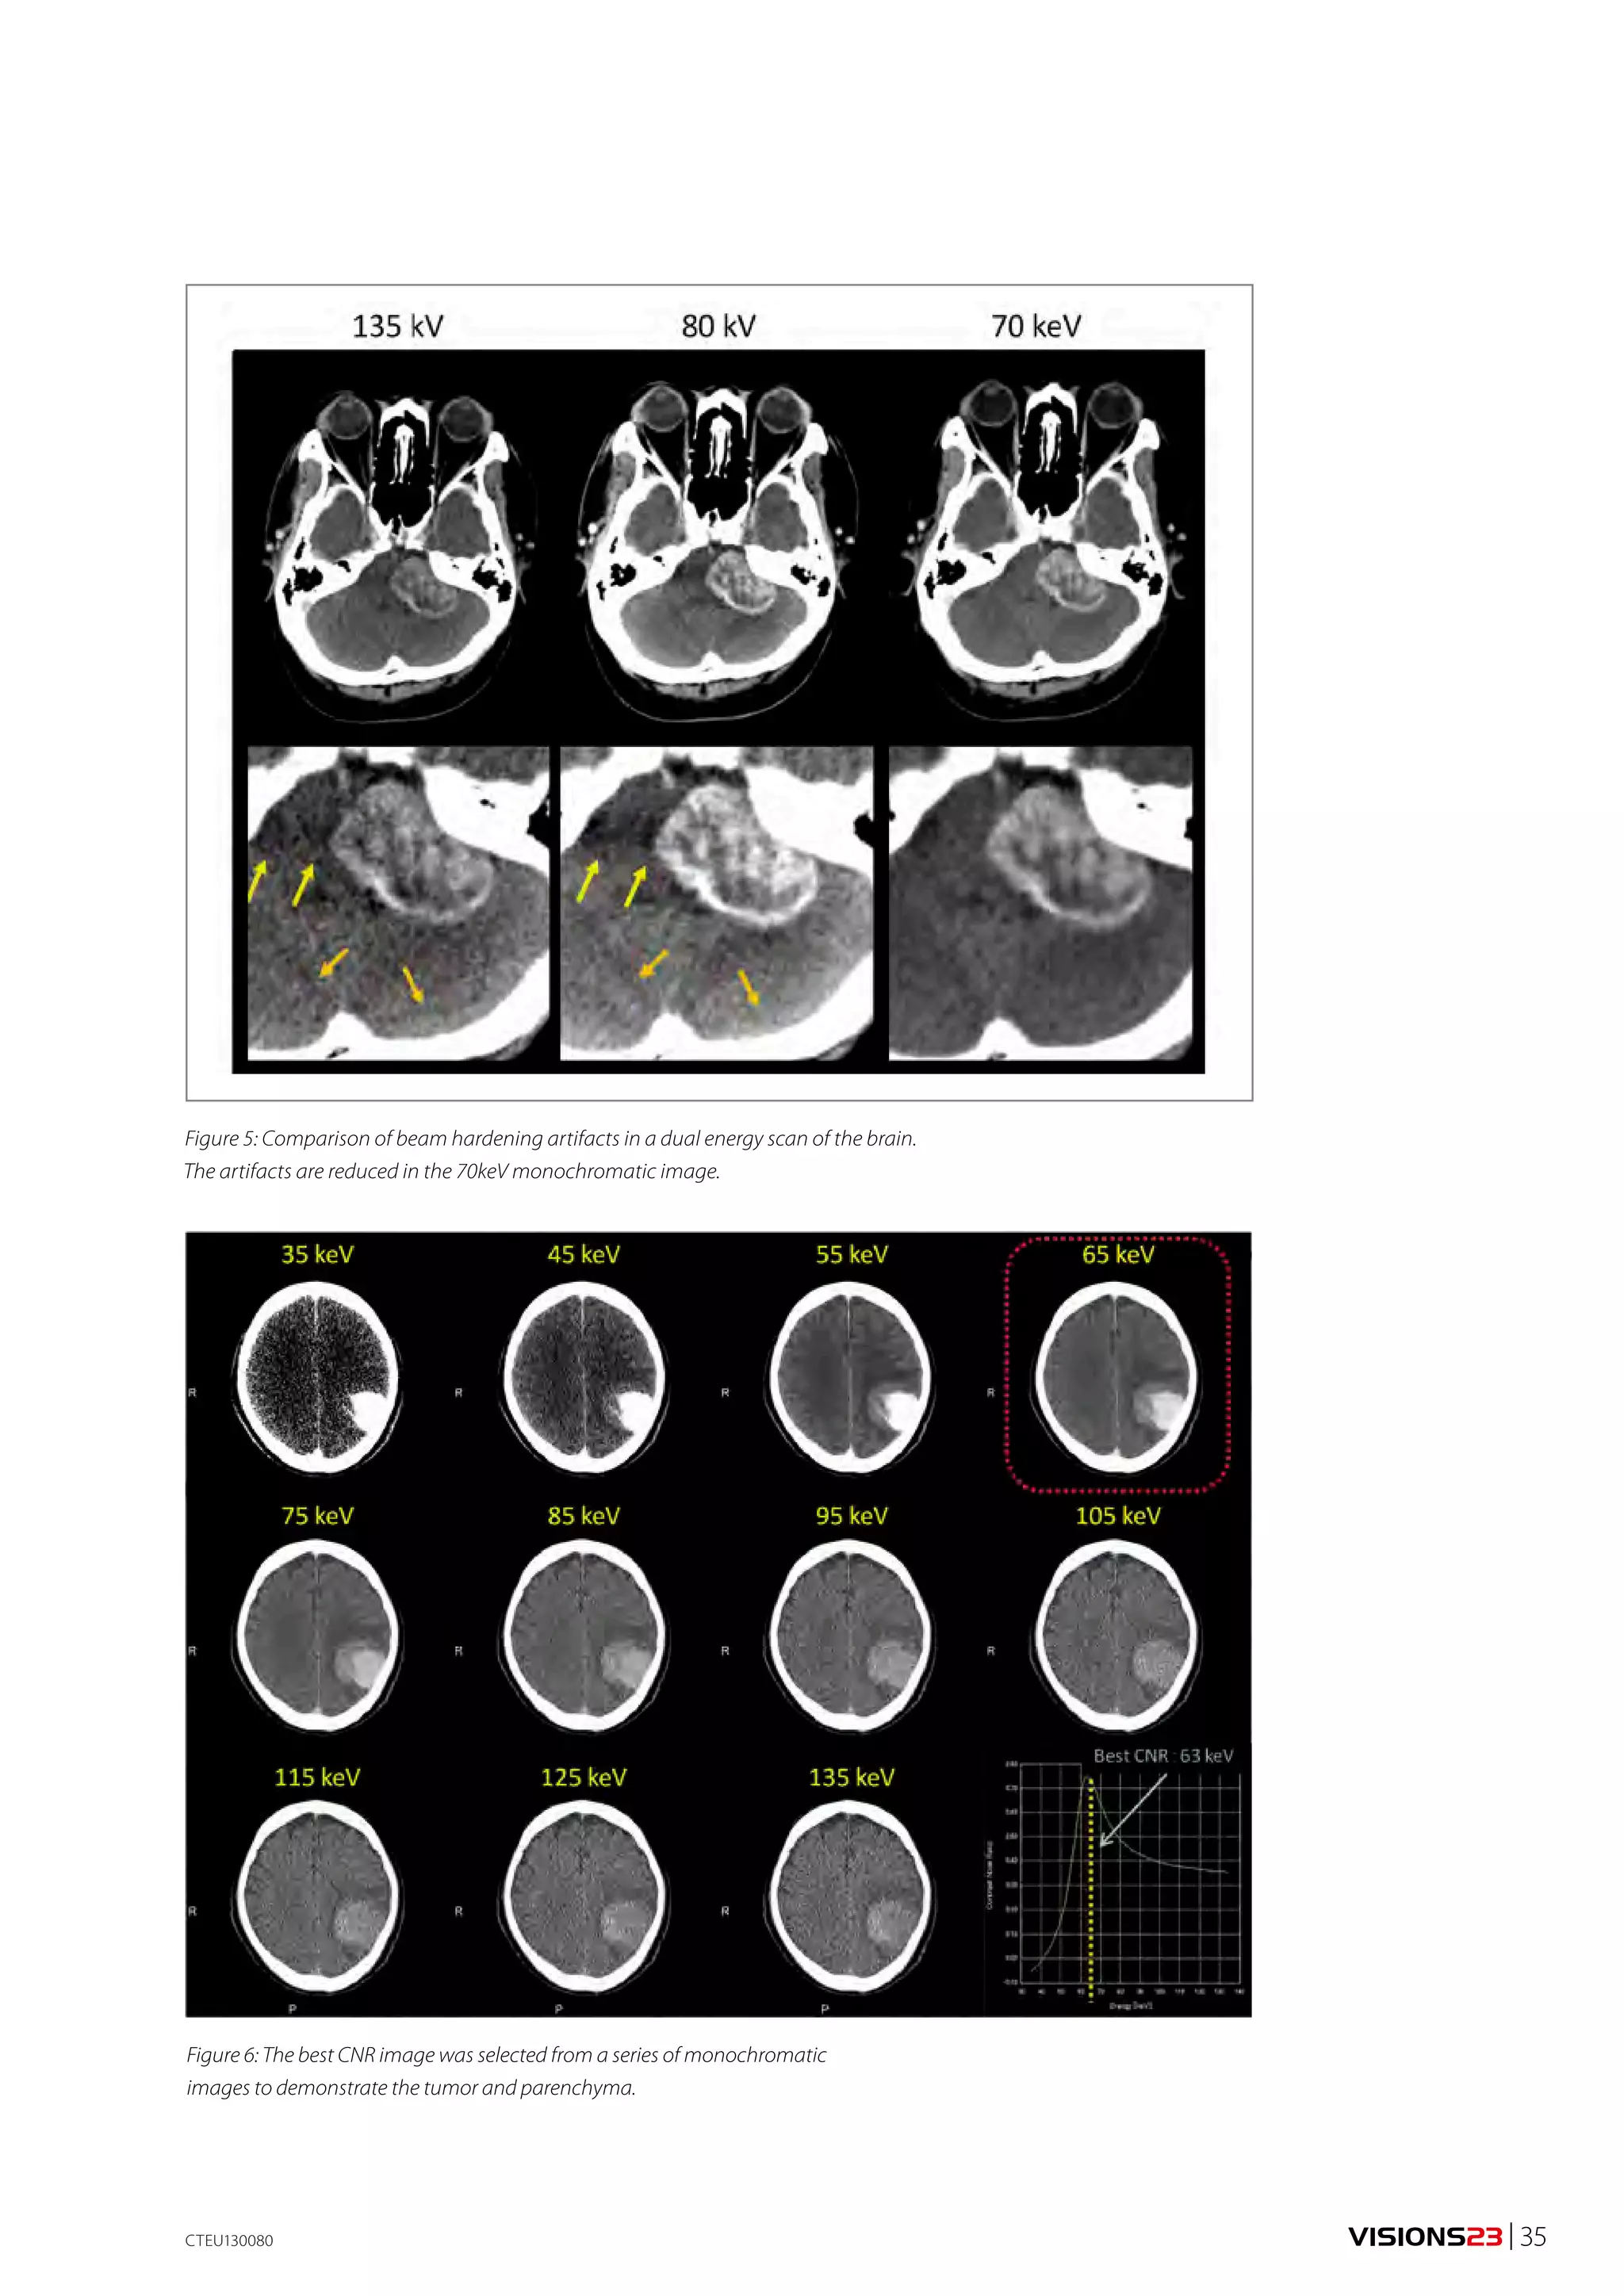

to scanning. Secondly, exposure can be manually turned

OFF in the upper part of gantry rotation that would

expose the ventral side of the patient and potentially

radiation sensitive areas such as breast tissue in females

(Fig. 1).

Figure 1: Tube exposure can be manually turned OFF in the

upper 180° of gantry rotation that would expose the ventral

side of the patient and potentially more radiation sensitive

areas such as breast tissue in females.

Although noise is reduced by automatic adjustment of

the mA settings on the low dose scan, the DE images will

often appear ‘noisier’ than the diagnostic standard expo-sure.

Radiologists need to recognize that the dataset will

provide images with low noise for general diagnosis in

addition to lower kVp data, which is used for the tissue

decomposition algorithm.

4. Post processing

Post processing of the image datasets produces not only